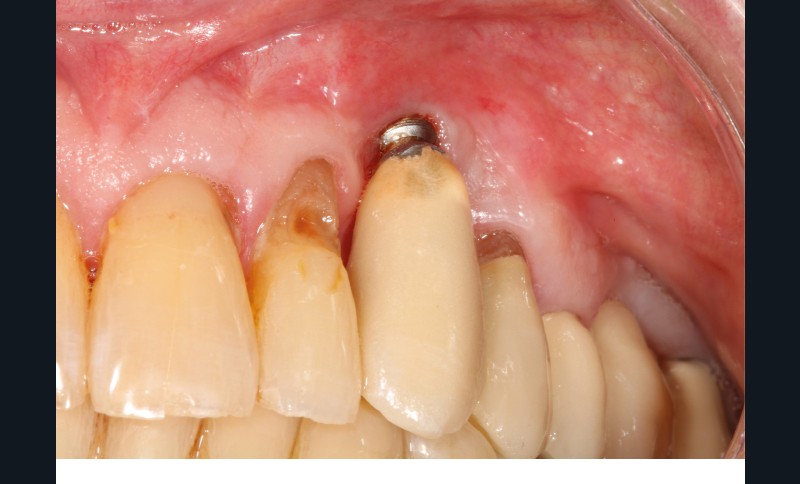

Le patient

- 70 ans

- Pas d’antécédents médicaux

- Ne fume pas

- Hygiène correcte

L’implant

- Site 23

- Mis en place il y a 12 ans